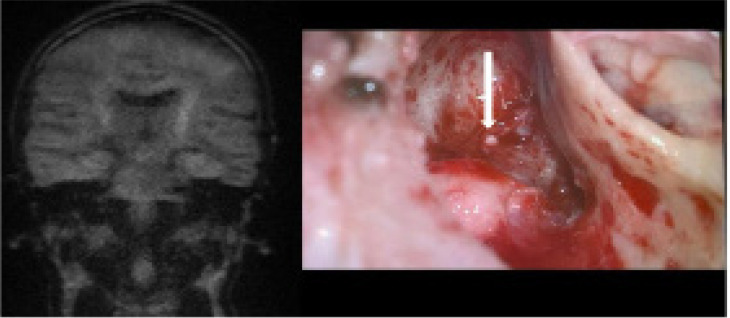

Results: Clinical and radiological concordance was found in 80% of patients. True positive results were observed in 77.5% of cases, while true negative results were noted in 2.5%. False positive results occurred in 8% of cases, mainly due to wax in the external auditory canal. False negative results were found in 12% of cases, often due to small or mural cholesteatomas. The sensitivity of MRI DWI non-EPI in detecting cholesteatoma was 87%.

Conclusions: MRI DWI non-EPI is an effective tool for detecting cholesteatoma recurrence, potentially avoiding unnecessary second-look surgeries. Awareness of false positive and negative results is crucial, and correlation of MRI findings with clinical examinations is recommended. To minimise false results, ear cleaning before MRI and repeated examinations at intervals are advised.